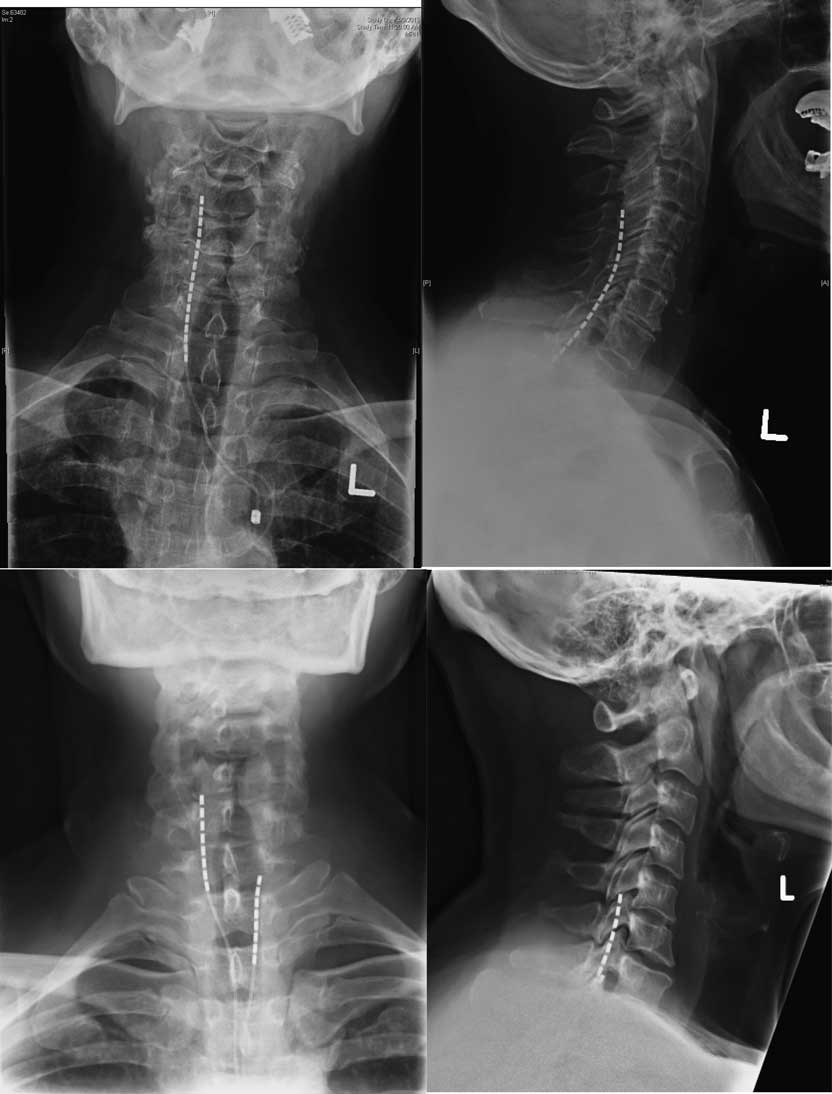

Treatment involved a trial period of 3 weeks, during which the programming of the device was adjusted and the patient’s response to the therapy was monitored. The trial electrodes were then removed and there was a mandatory washout period of at least two weeks. Permanent implantation followed successful trials, defined as a visual analogue scale (VAS) decrease ≥50% or a sufficiently large pain reduction to have a significant effect on the patient’s quality of life. The stimulation technique was chosen was based the geographic distribution of the pain as well as intraoperative test stimulation results. In general, for the upper limb, nerve root stimulation was used in patients where the pain area was limited to one to four dermatomes. Electrodes were anchored to the thoracolumbar fascia using the standard technique with Boston Scientific’s Clik anchors. Examples of the placement of SCS and DNRS electrodes in the cervical spine are shown in Figures 1 and 2, respectively.

Figure 2 Anteroposterior and lateral X rays for three patients showing placement of DNRS electrodes.